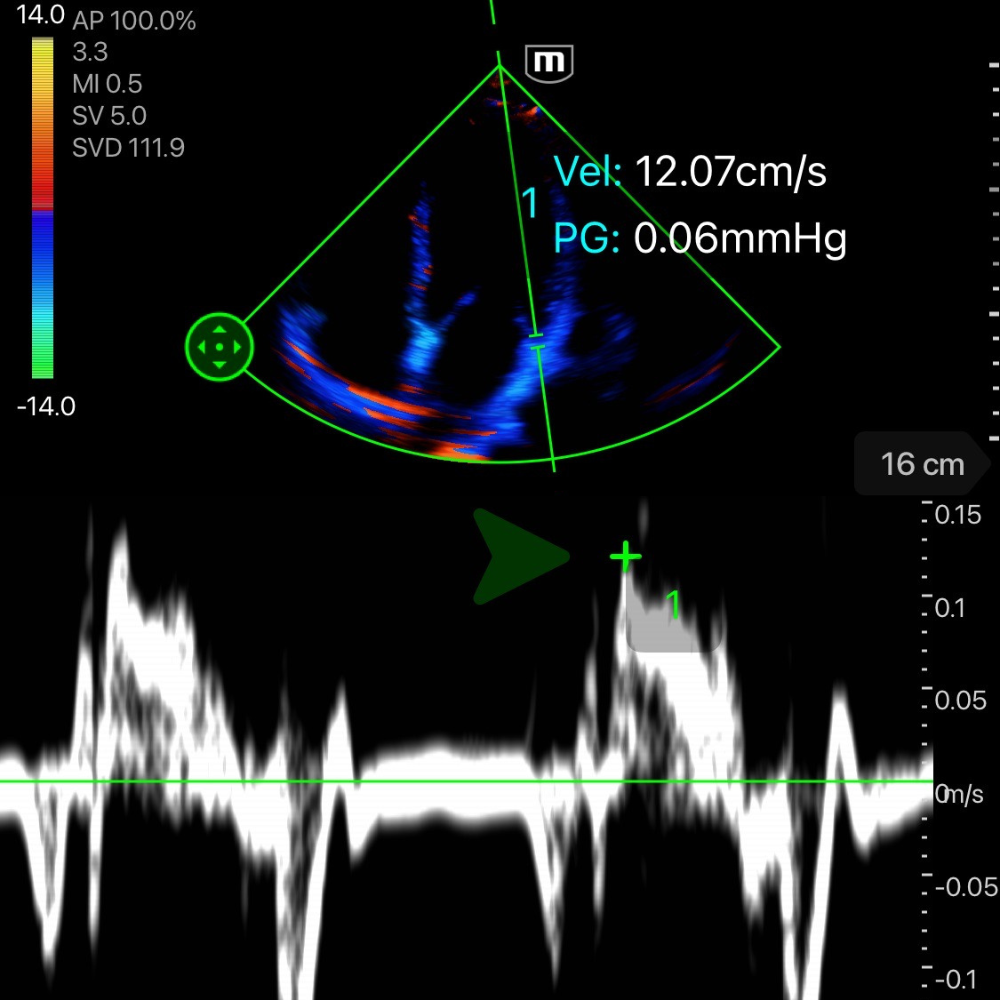

🧮 Calcul de l'onde S'

L’onde S’ mesurée en Doppler Tissulaire (TDI) au niveau de l’anneau mitral permet une evaluation indirecte de la FEVG avec une corrélation satisfaisante.

Comment mesurer l’onde S’

-

Vue apicale 4 cavités.

Activer le Doppler Tissulaire (TDI).

Placer le curseur sur l’anneau mitral latéral.

Identifier et mesurer le pic de l’onde S’ (vélocité systolique).

Interprétation

S’ < 8 cm/s → dysfonction systolique du VG.

S’ 8-10 cm/s → fonction réduite ou zone grise.

S’ > 10 cm/s → fonction systolique généralement conservée.